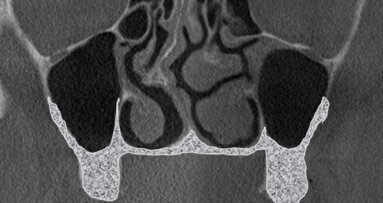

W 2015 r. polski autor Radosław Jadach przedstawił pracę oryginalną, w której opisuje zabieg podniesienia dna zatoki szczękowej z dostępu od strony podniebiennej jako metody alternatywnej.7 Zabieg wykonano u 39 pacjentów. Autor opisuje również własną klasyfikację, na podstawie której łatwiejsze będzie podjęcie decyzji odnośnie tego która z metod podniesienia dna zatoki szczękowej będzie bardziej odpowiednia dla danego przypadku klinicznego. Klasyfikację tę autor stworzył na podstawie analizy 200 badań tomografii komputerowej wiązką stożkową (CBCT). Klasyfikacja przedstawia podział ze względu na grubość blaszki kostnej od strony przedsionkowej i podniebiennej w sposób następujący:

Ryc. 2 a_Wytworzenie okna kostnego od strony podniebiennej, uwidaczniając nienaruszoną membranę Schneidera.

Ryc. 2 b_Wytworzenie okna kostnego od strony podniebiennej, uwidaczniając nienaruszoną membranę Schneidera.